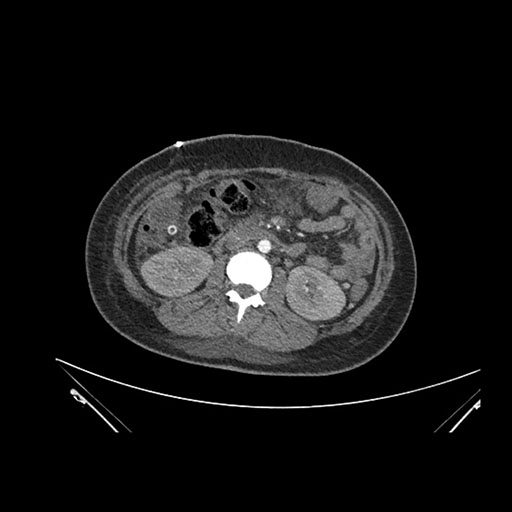

Axial Venous